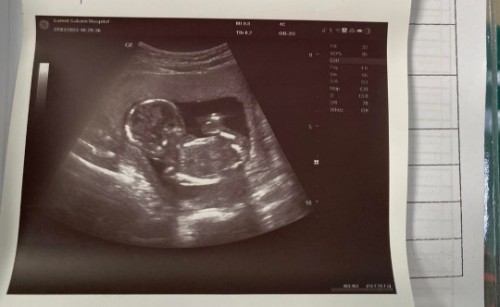

ท้องแรก15w3d ตัวน้องใช่ไหมคะ

สอบถามแม่ๆหน่อยค่ะ คือไม่แน่ใจเลยว่าใช่ตัวน้องไหมเพราะตื่นเต้นดีใจด้วยที่เห็นเป็นตัวน้องแล้ว นี่คือตัวน้องแล้วใช่ไหมคะ

ใช่ 100% ค่ะ 😂😂😂 เป็นตัวขนาดนี้ 555555555 แม่หยุดตื่นเต้นก๊อนนน